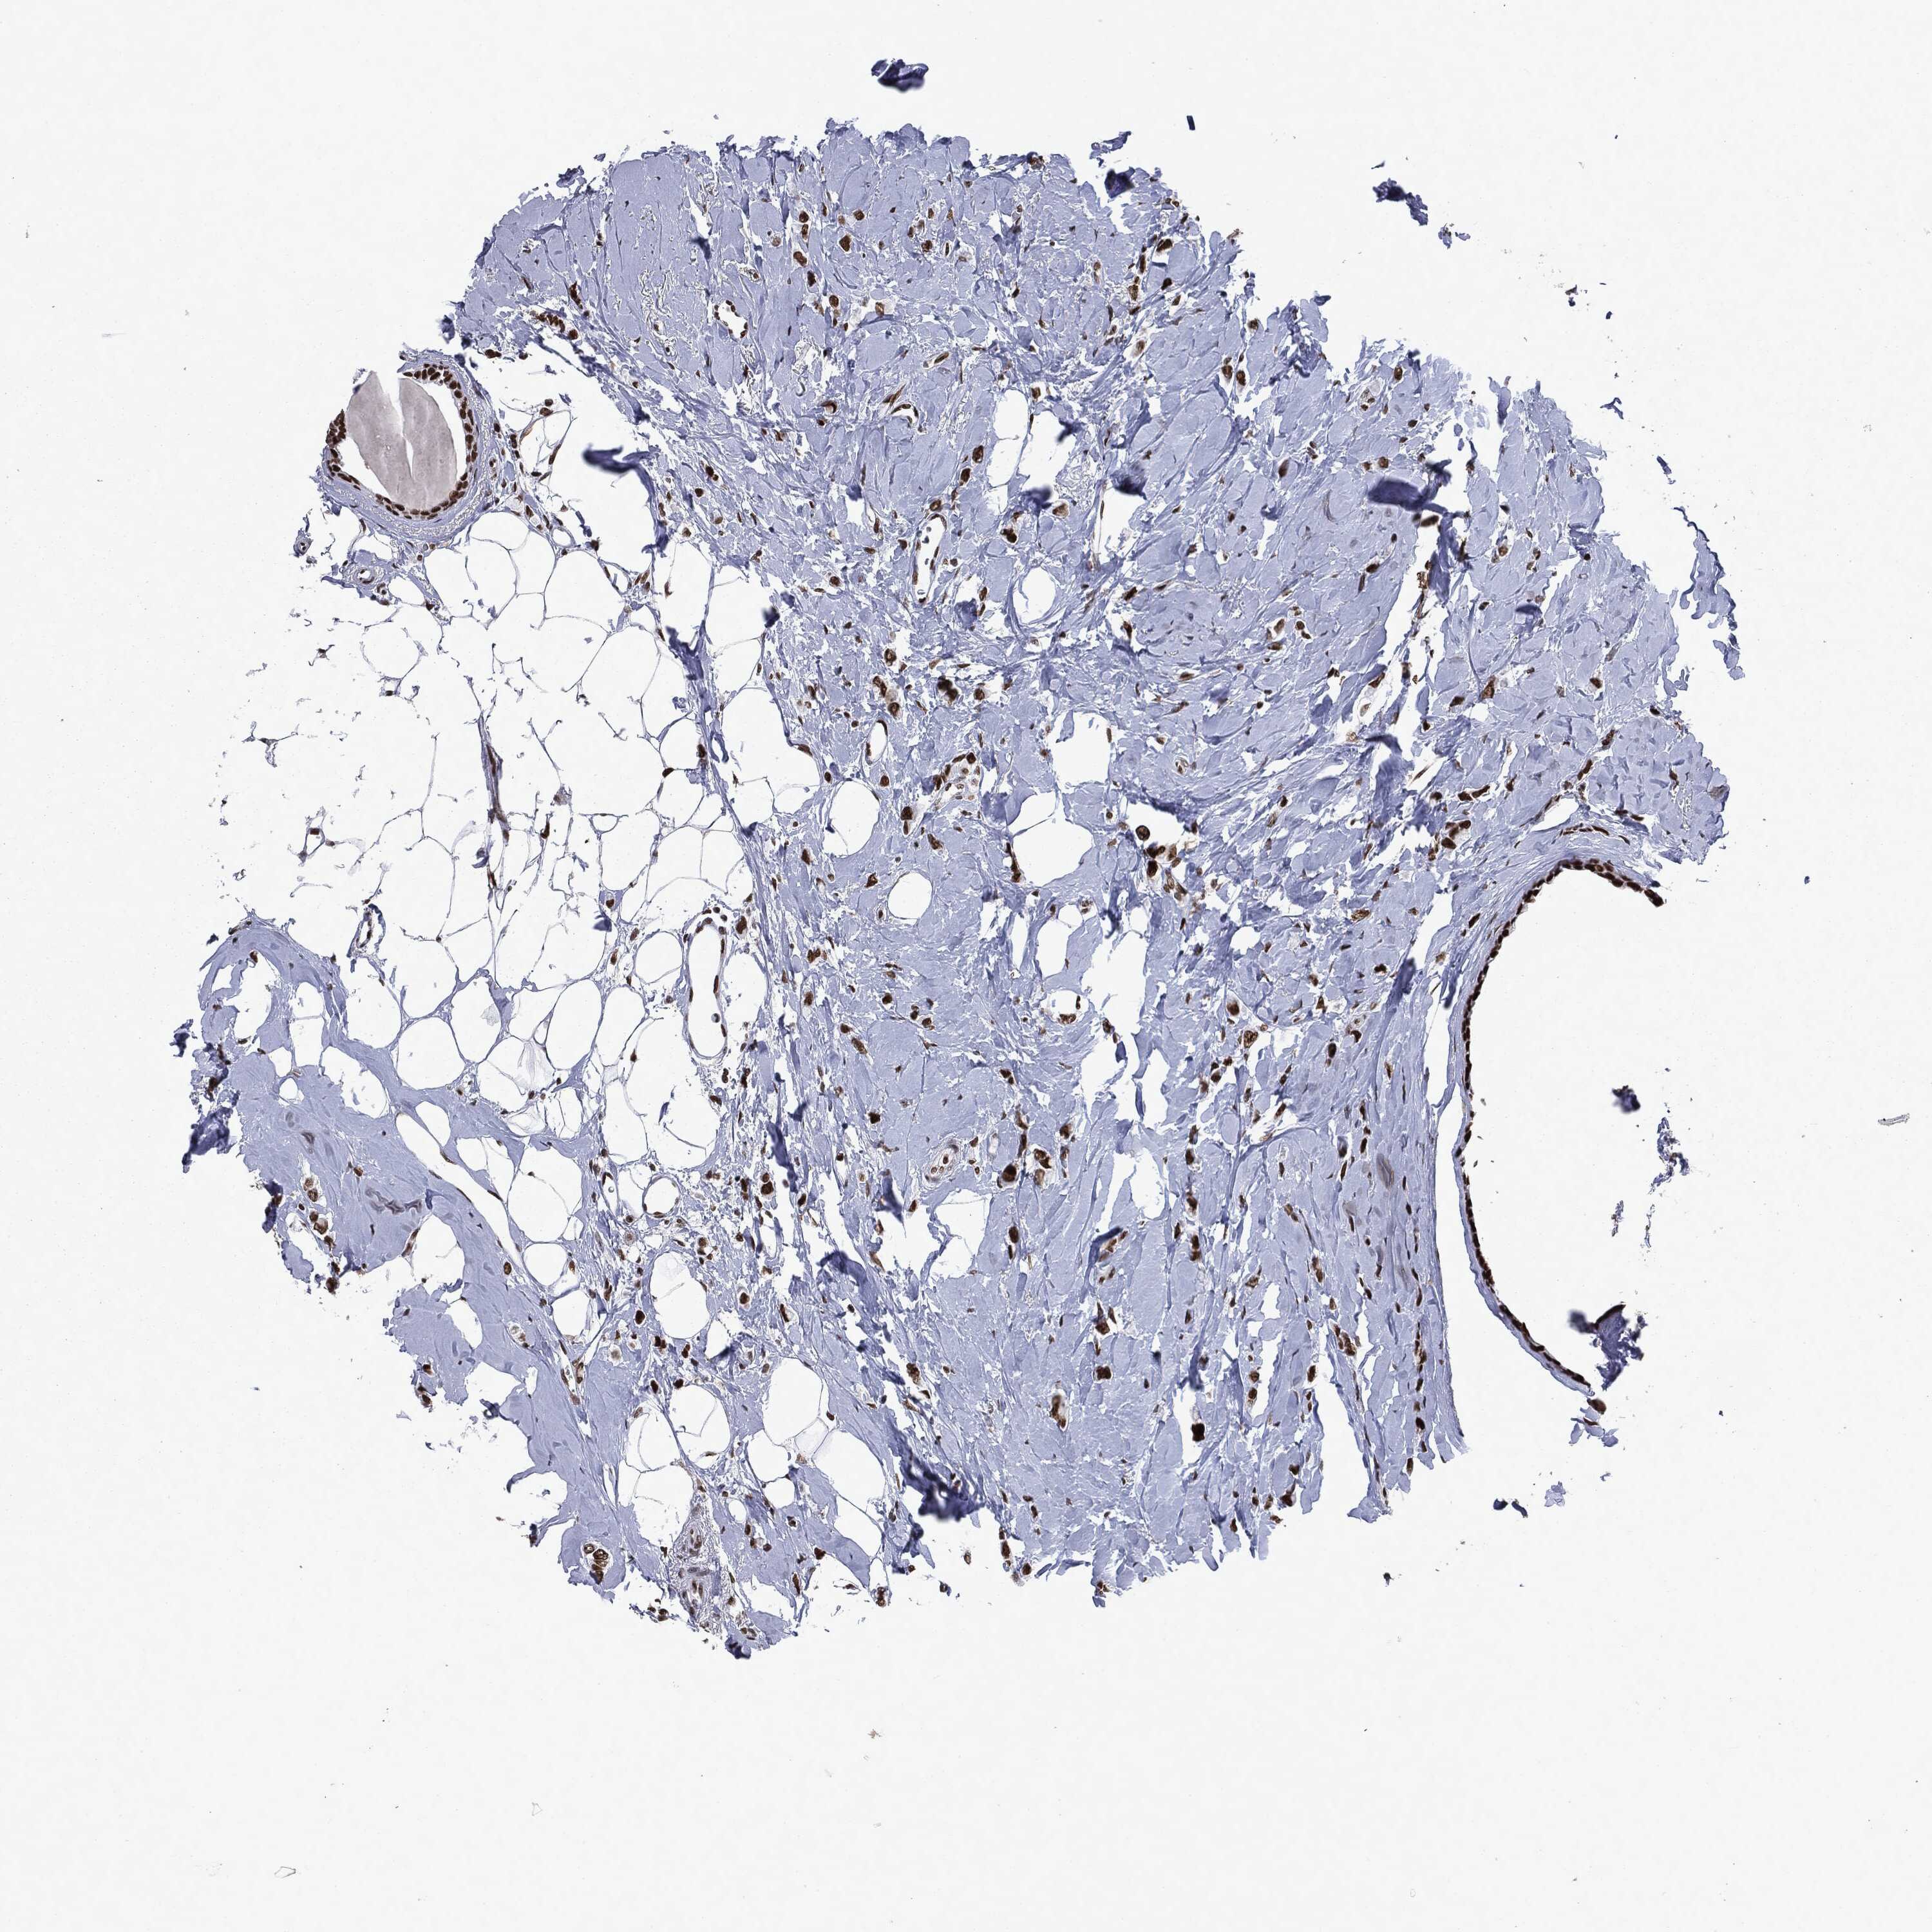

BRCA TCGA BRCA VALIDATION PROTEIN EXPRESSION

ANTIBODIES

AND

VALIDATION